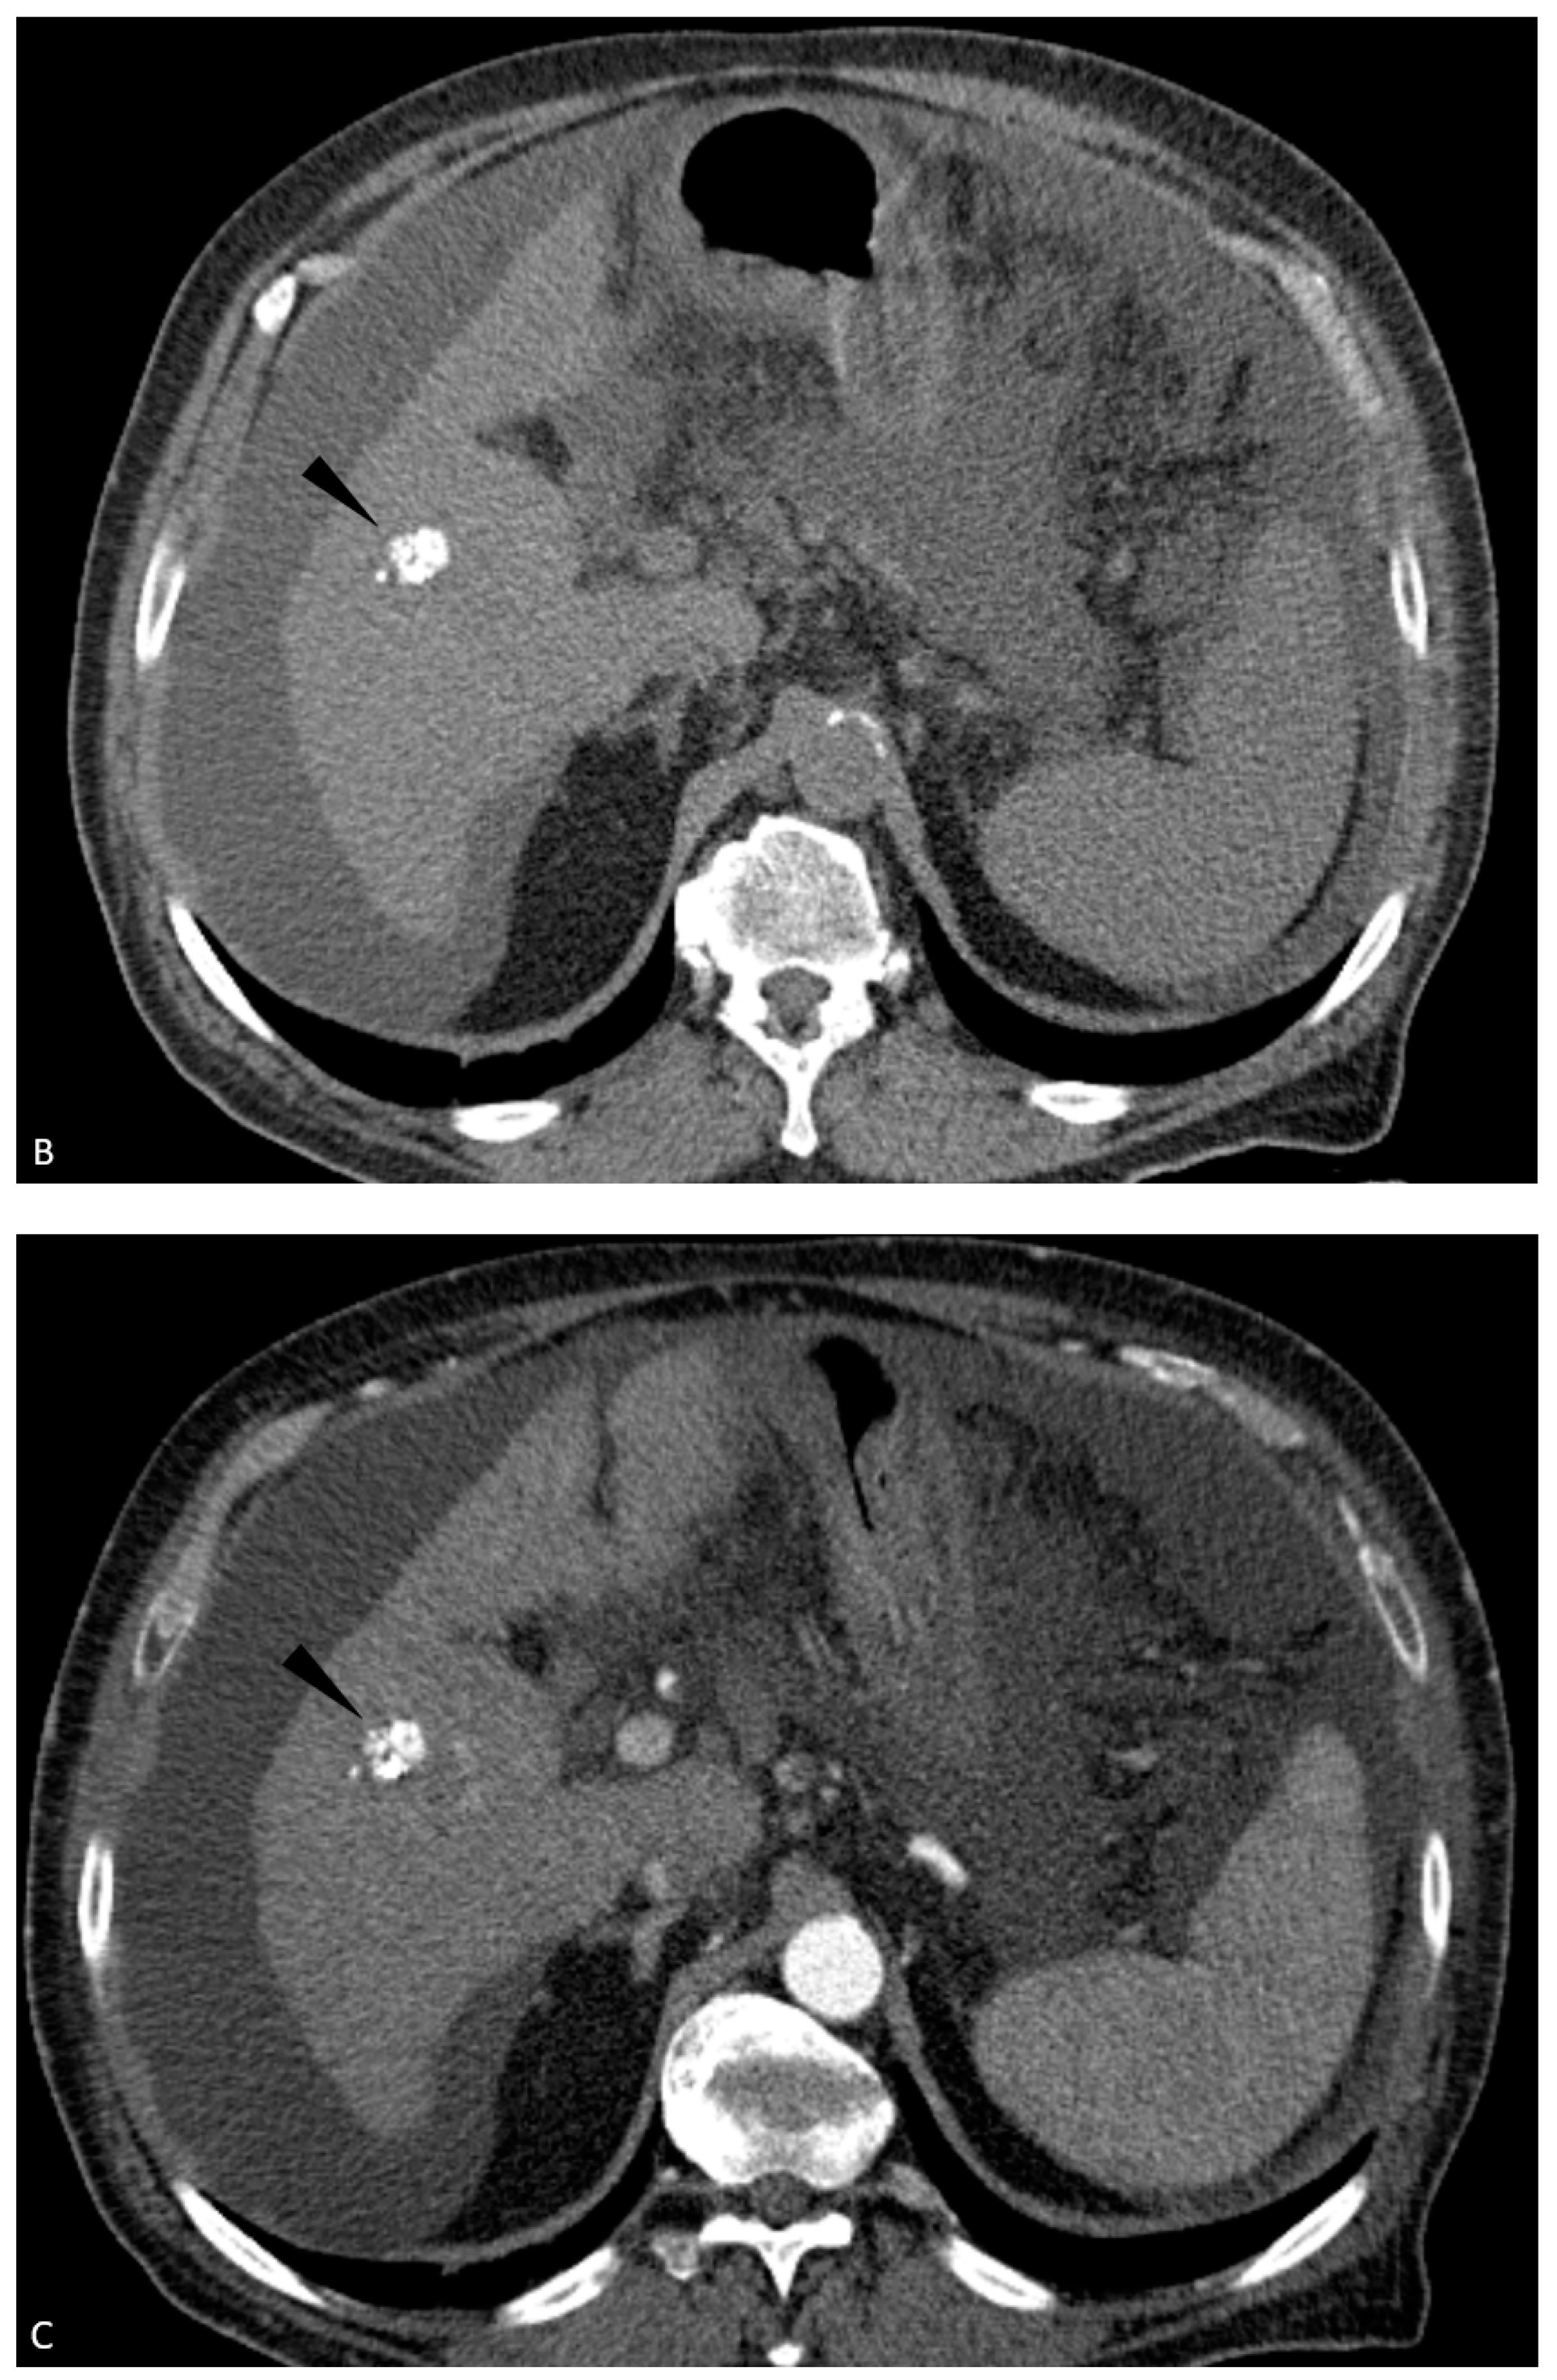

| 7 | CEUS | Target | LR-treated | CT called residual tumor, follow-up CT showed the area was perfusional, not disease (Figure 3) |